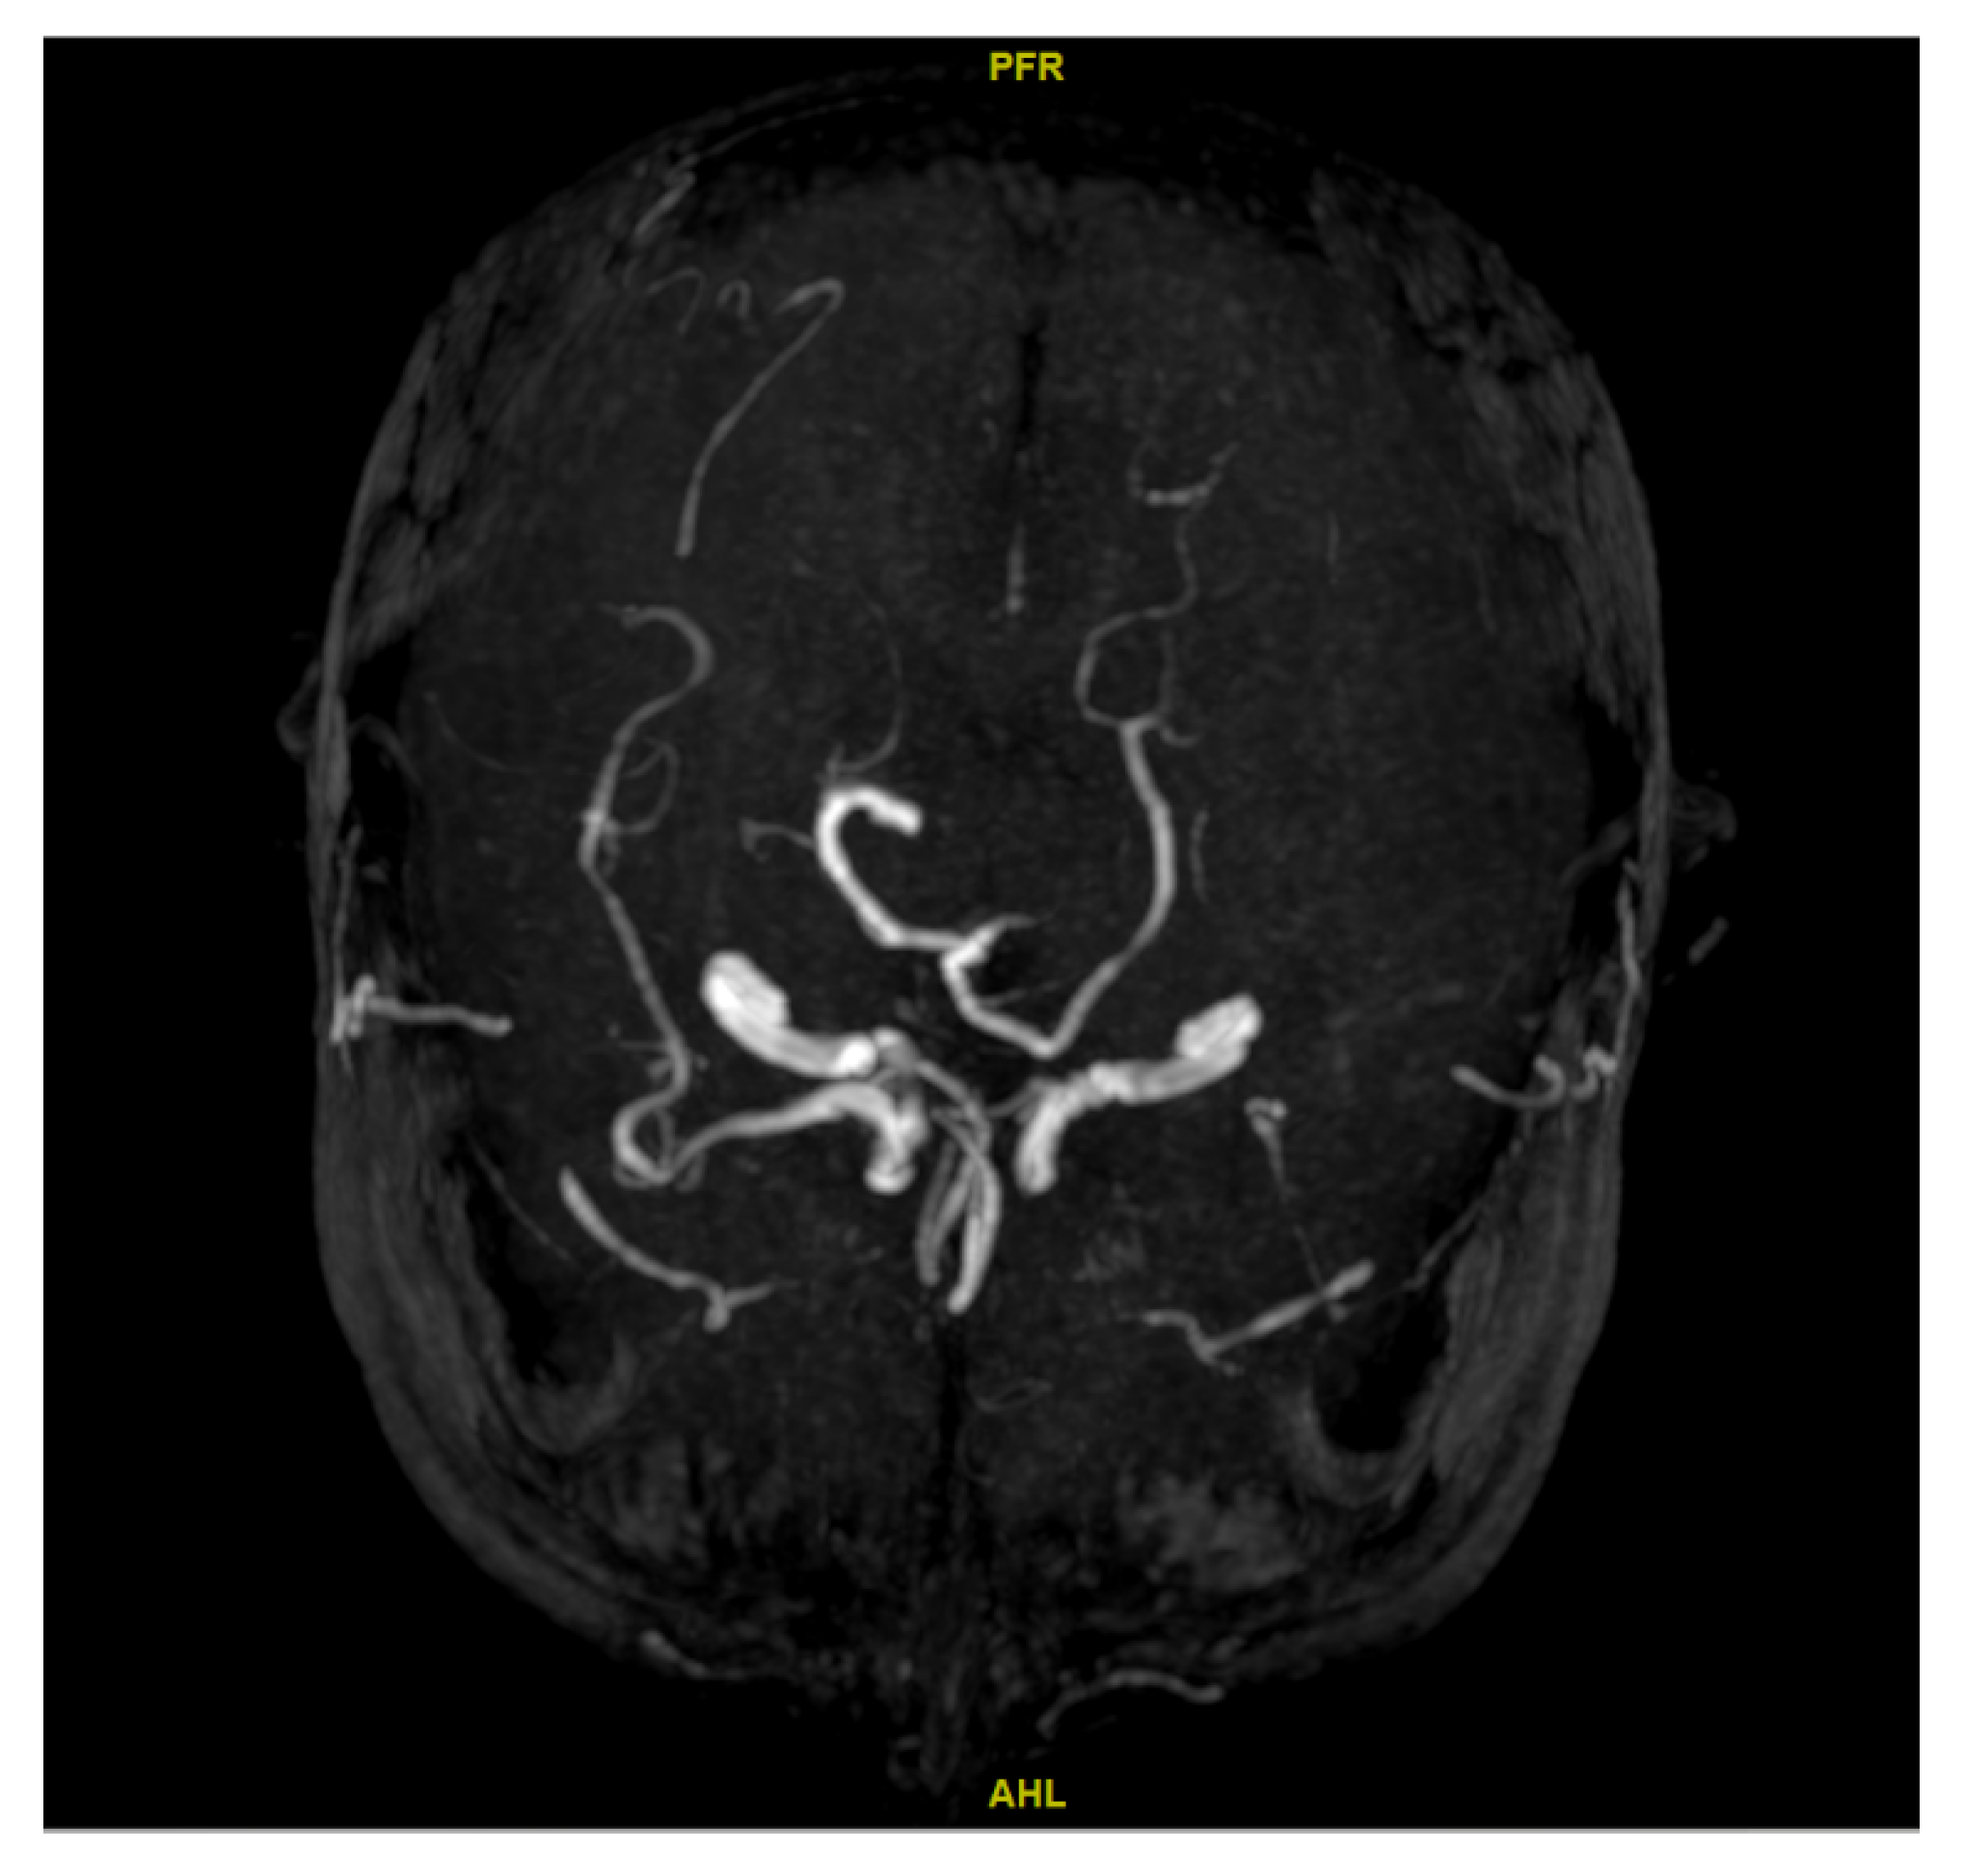

2.3. Determination of CBF

2.4. Ascertainment of Cerebral Artery Stenosis